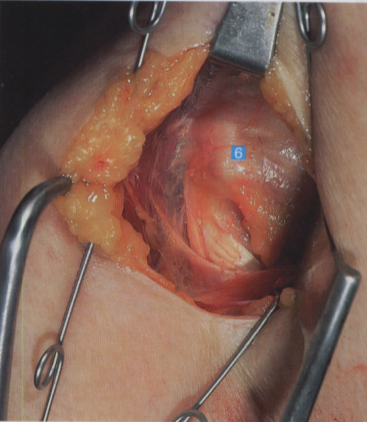

牵开肱二头肌,显露底层的背阔肌及横行的肩胛下肌

6. 肩胛下肌筋膜;7. 肱骨头;